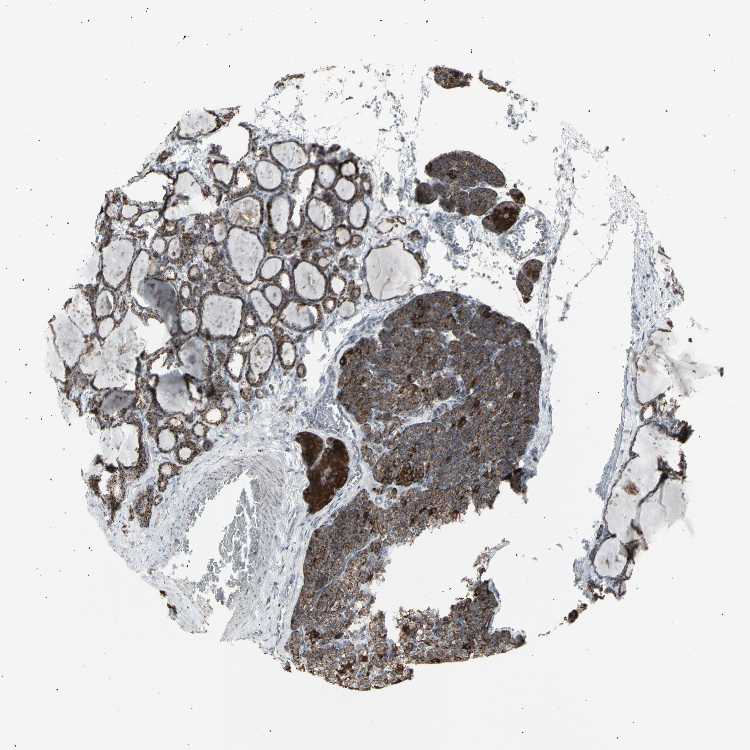

TISSUE PRIMARY DATA PARATHYROID GLAND Show tissue menu

Parathyroid gland

PARATHYROID GLAND - Expression summary

PARATHYROID GLAND - Antibody stainingi

Antibody staining in the annotated cell types in the current human tissue is reported as not detected, low, medium, or high, based on conventional immunohistochemistry profiling in selected tissues. This score is based on the combination of the staining intensity and fraction of stained cells.

Each image is clickable and will lead to virtual microscopy that enables deeper exploration of all samples and also displays staining intensity scores, fraction scores and subcellular localization as well as patient and tissue information for each sample.

Antibody HPA008214Antibody HPA011144

Glandular cells MediumHigh